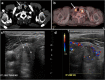

Focal and diffuse thyroid abnormalities are commonly encountered during the interpretation of computed tomography (CT) exams performed for various clinical purposes. These findings can often lead to a diagnostic dilemma, as the CT reflects the nonspecific appearances. Ultrasound (US) examination has a superior spatial resolution and is considered the modality of choice for thyroid evaluation. Nevertheless, CT detects incidental thyroid nodules (ITNs) and plays an important role in the evaluation of thyroid cancer. In this pictorial review, we cover a wide spectrum of common and uncommon, incidental and non-incidental thyroid findings from CT scans. We also discuss the most common incidental thyroid findings, best practices for their evaluation, and recommendations for their management. In addition, we explore the role of imaging in the assessment of thyroid carcinoma (before and after treatment) and preoperative thyroid goiter, as well as localization of ectopic and congenital thyroid tissue.

Teaching points: • Thyroid disorders tend to have non-specific CT appearances. • ITNs are common on neck CT. • ITN management depends on nodule size, age, health status, lymphadenopathy, and invasion. • CT is used in assessment of cancer extension, mass effect, invasion, and recurrence. • CT plays a role in preoperative planning in patients with symptomatic goiter.